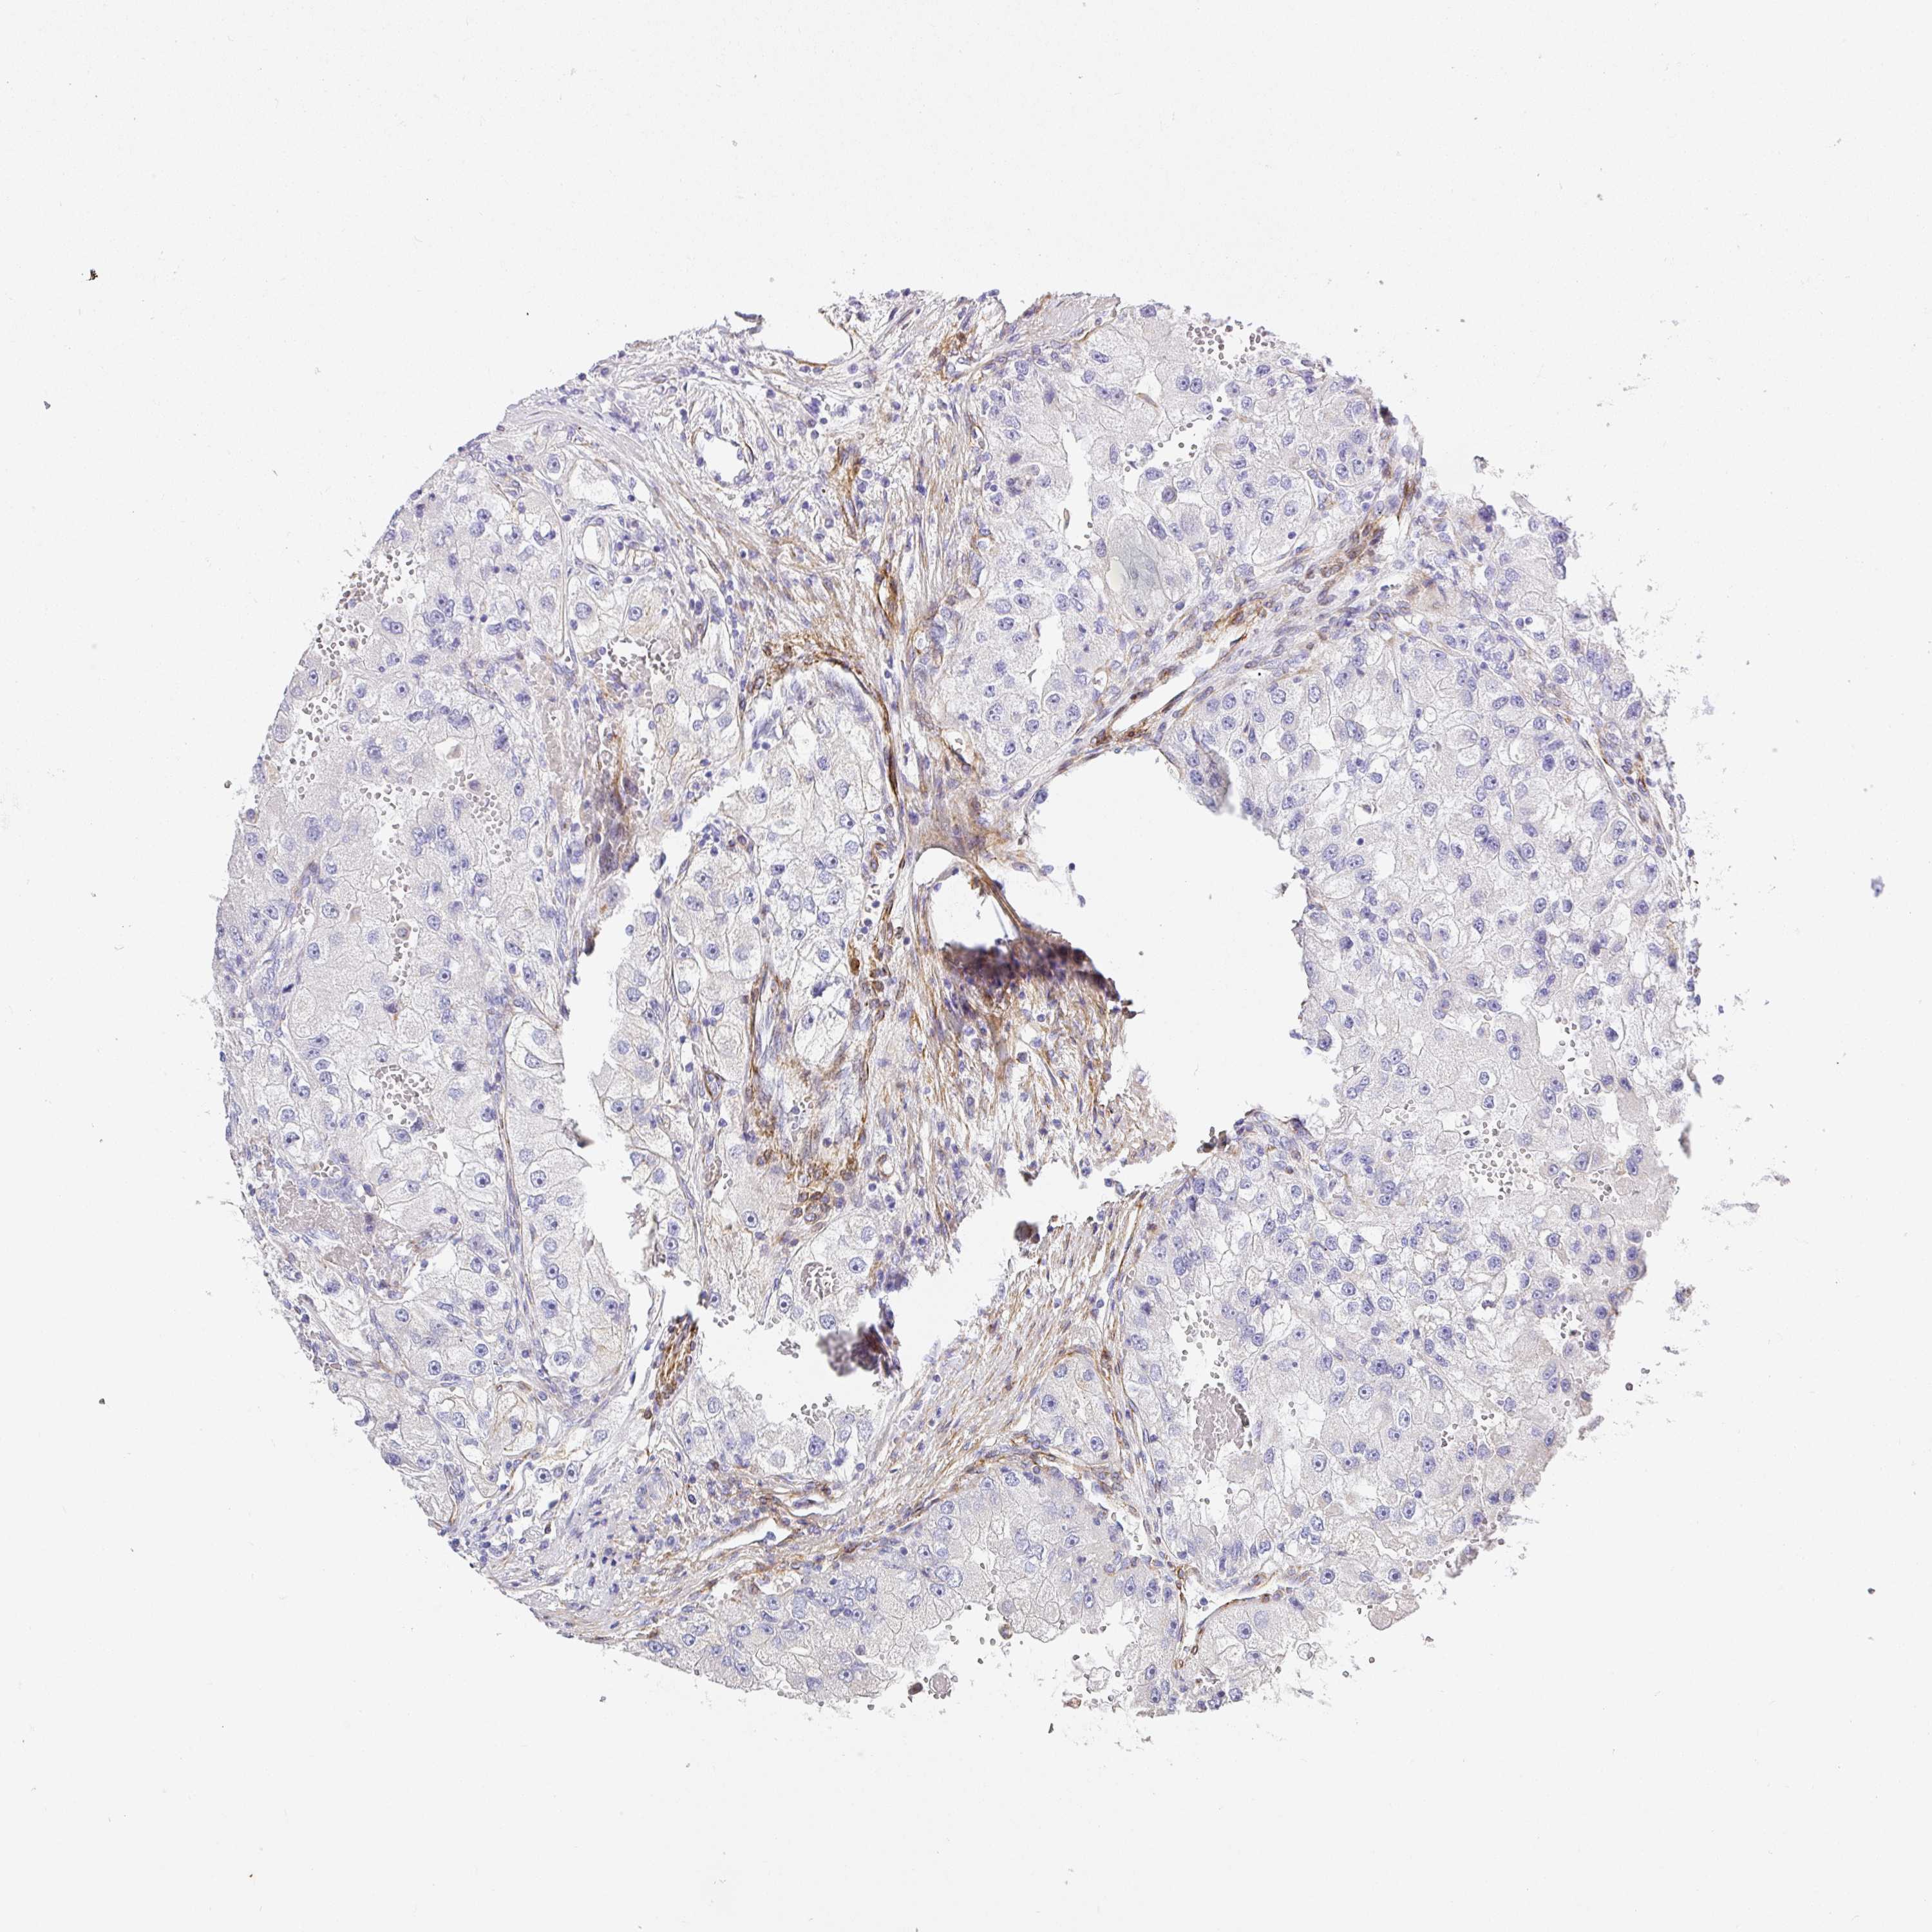

KIDNEY RENAL CLEAR CELL CARCINOMA (TCGA) - Interactive survival scatter ploti

The Survival Scatter plot shows the clinical status (i.e. dead or alive) for all individuals in the patient cohort, based on the same data that underlies the corresponding Kaplan-Meier plots. Patients that are alive at last time for follow-up are shown in blue and patients who have died during the study are shown in red.

The x-axis shows the expression levels (FPKM) of the investigated gene in the tumor tissue at the time of diagnosis. The y-axis shows the follow-up time after diagnosis (years). Both axes are complimented with kernel density curves demonstrating the data density over the axes. The top density plot shows the expression levels (FPKM) distribution among dead (red) and alive patients (blue). The right density plot shows the data density of the survived years of dead patients with high and low expression levels respectively, stratified using the cutoff indicated by the vertical dashed line through the Survival Scatter plot. This cutoff is automatically defined based on the FPKM cutoff that minimizes the p-score. The cutoff can be changed by dragging the vertical line or by entering a cutoff value in the square labeled "Current cut-off".

Under the Survival Scatter plot the p-score landscape (black curve; left axis) is shown together with dead median separation (red curve; right axis). Dead median separation is the difference in median mRNA expression between patients who have died with high and low expression, respectively. It is calculated as follows: median FPKM expression of dead patients with high expression - median FPKM expression of dead patients with low expression. This is intended to aid the user in visually exploring custom cutoffs and the associated p-scores and dead median separation.

Individual patient data is displayed and can be filtered by clicking on one or more of the category buttons on the top of the page. Categories describing expression level and patient information include: high, low, alive, dead, female, male and tumor stages. The scale of the x-axis can be toggled between linear and log-scale by clicking on the "x log" button. Mouse-over function shows TCGA ID, patient information and mRNA expression (FPKM) for each patient.

& Survival analysisi

Kaplan-Meier plots summarize results from analysis of correlation between mRNA expression level and patient survival. Patients were divided based on level of expression into one of the two groups "low" (under cut off) or "high" (over cut off). X-axis shows time for survival (years) and y-axis shows the probability of survival, where 1.0 corresponds to 100 percent.

SLC25A17 is potential prognostic, high expression is favorable in Kidney Renal Clear Cell Carcinoma (TCGA)

Best expression cut offi

Based on the FPKM value of each gene, patients were classified into two groups and association between prognosis (survival) and gene expression (FPKM) was examined. The best expression cut-off refers the FPKM value that yields maximal difference with regard to survival between the two groups at the lowest log-rank P-value. Best expression cut-off was selected based on survival analysis .

When clicking on this number, the vertical dashed line indicating cut-off, the interactive survival plot, and the Kaplan-Meier curve will be adjusted to show results based on the best expression cut-off.

: 10.44

TCGA RNA samplesi

RNA-seq data is reported as average FPKM (number Fragments Per Kilobase of exon per Million reads), generated by the The Cancer Genome Atlas (TCGA) .

Normal distribution across the dataset is visualized with box plots, shown as median and 25th and 75th percentiles. Points are displayed as outliers if they are above or below 1.5 times the interquartile range. FPKM values of the individual samples are presented next to the box plot.

Average pTPM 11.5

Number of samples 521